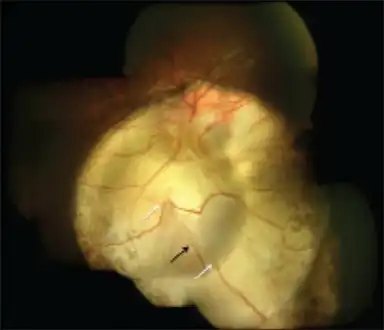

| Coloboma in a 16-year-old female | |

Typically a coloboma appears oval- or comet-shaped with round end towards the centre. There may be a few vessels (retinal or choroidal) at the edges. The surface may have irregular depression.

Right fundus with small coloboma at the inferior edge of the nerve that is vertically elongated.